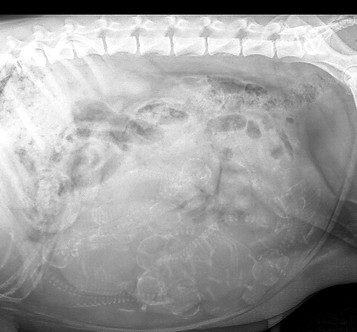

Once a mating has taken place, the mother has an ultrasound at around day 30 from date of mating and this will confirm a pregnancy, but cannot accurately determine number of puppies at this stage. The mothers nutrition changes at this point to a higher energy level with attention to their weekly weight gain. Next is an x-ray to take place at around days 50-55 once ossification has occurred, which is bone formation of the puppies, the vet can advise on approximate number of puppies so we know what to expect and we start to prepare for the birth.